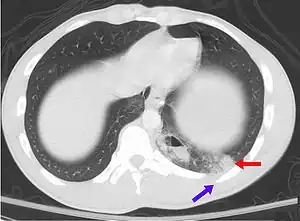

![]() | |

| A CT scan showing a pulmonary contusion (red arrow) accompanied by a rib fracture (blue arrow) | |